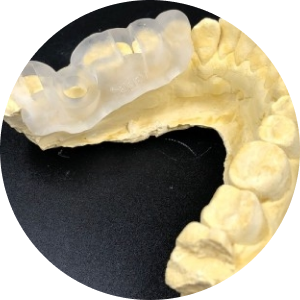

Nidaan – UniGuide 3D Printing

Precision 3D-printed guides manufactured.

Strict quality control to ensure perfect fit.

Compatible with leading implant systems.